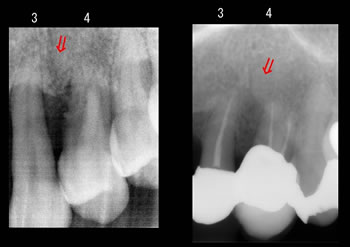

反対側の左です、、、

レントゲンの装置が変わっておりまして、、、

さらに最近も新しくなったので、同じ条件で撮影するのが難しいです!汗! |

再生された骨の縁に白いライン(歯槽硬線)がありますよね!

重要!

左の方は骨の縁がモヤモヤっと虫に喰われてみたいにぼんやりしてますが、右の治療後は再生されたうえに歯槽硬線がハッキリ見え、かなり安定しています! |